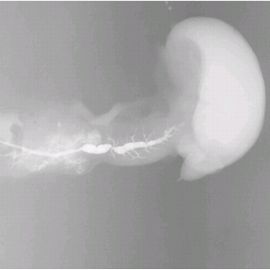

術後組織造影画像